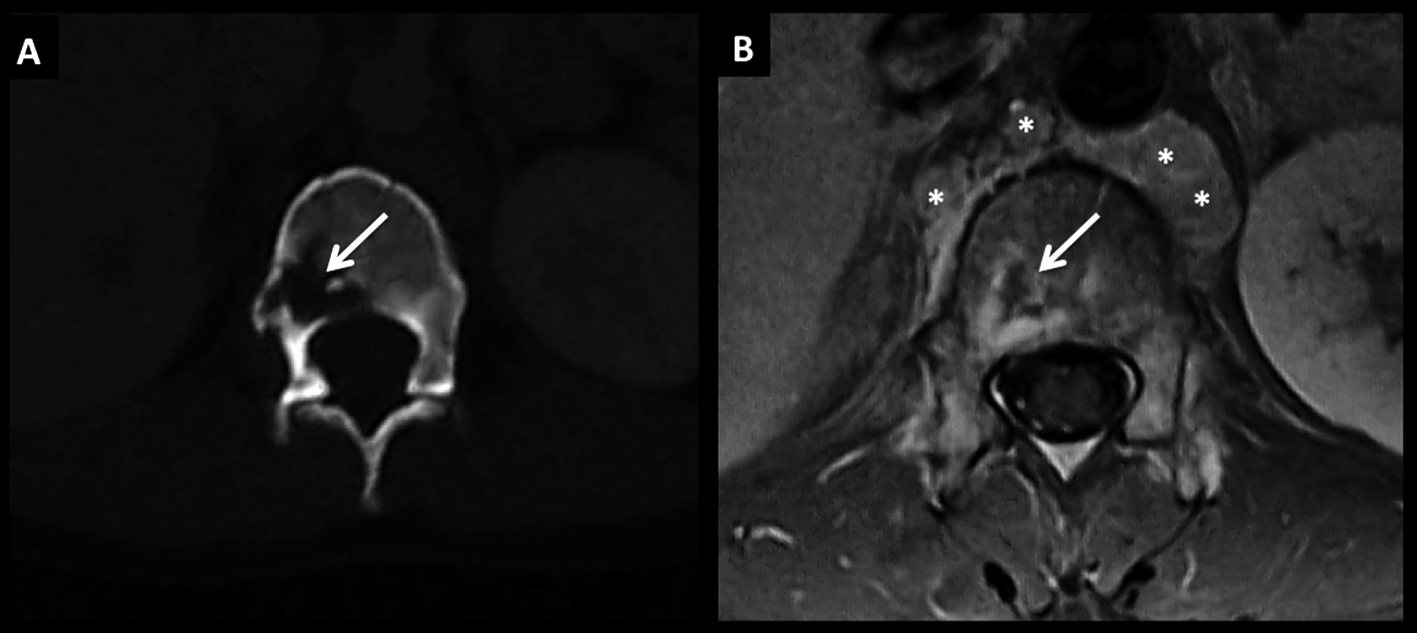

LNH, lesión ósea única, compromiso secundario.

Se muestra el caso de un paciente con LNH sistémico con múltiples adenomegalias retroperitoneales (*) y que en el estudio de estadificación inicial presentó una lesión focal ósea, única, en el cuerpo de T12.

En TC (A) la lesión es claramente lítica, ubicada en el cuerpo vertebral, con escasa esclerosis asociada y con contornos irregulares y destrucción trabecular.

En RM, secuencia SE T1 post-contraste en el plano axial (B) la lesión muestra un centro con necrosis y realce heterogéneo periférico.